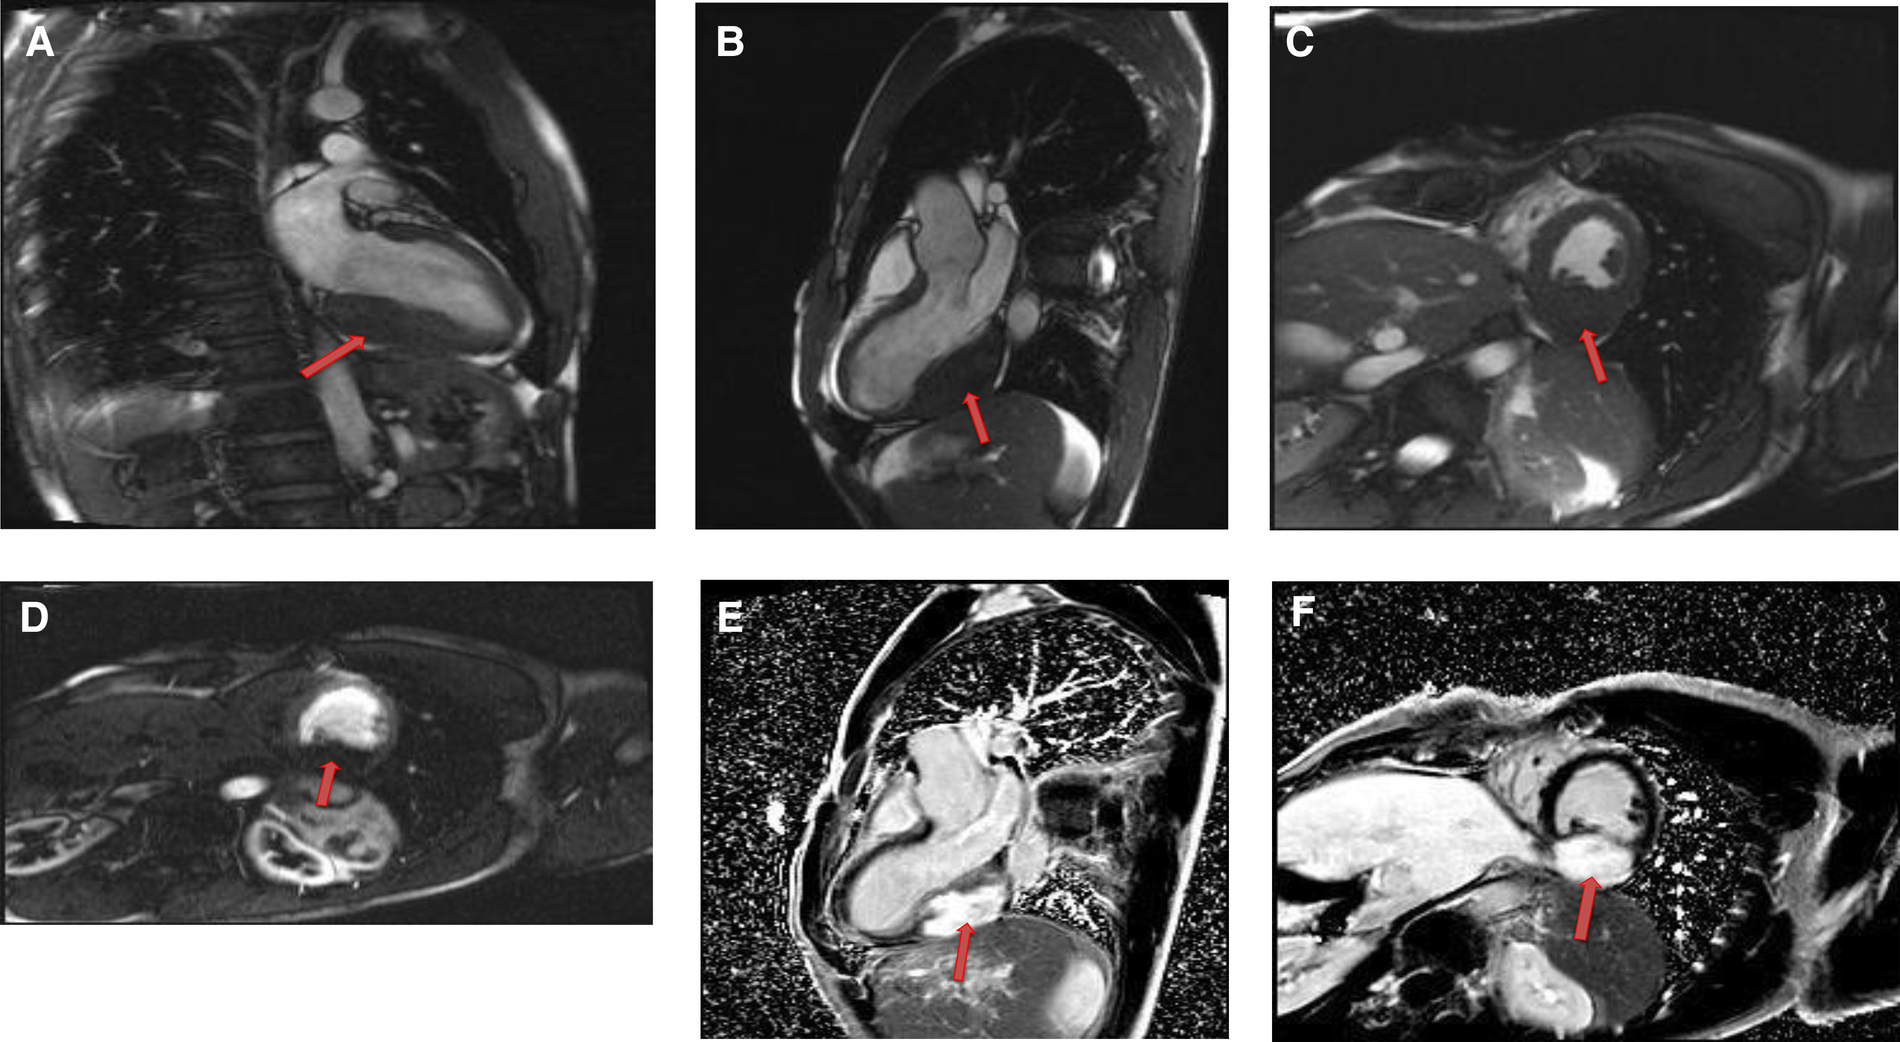

Cardiac myxomas typically have a heterogeneous appearance on CMR because of varying components of myxoid, cystic, hemorrhagic, fibrotic, and calcified material (27). As they are highly mobile tumors, cine imaging is often very helpful in the work-up of myxomas. Tumor mobility, including mitral valve prolapse causing obstruction, may be seen on the cine images. On SSFP cine sequences myxomas are usually hypointense relative to the blood pool and hyperintense relative to the myocardium (28). They are isointense/hypointense to the myocardium on T1- weighted images and hyperintense on T2-weighted images likely due to high extracellular water contents. There may be associated regions of necrosis and hemorrhage that appear hypointense on both T1- and T2-weighted images (29). Most of the myxomas demonstrate at least some mild patchy enhancement on the first pass perfusion images. Myxomas usually show moderate to high, heterogeneous enhancement on LGE images (Table 1 and Figures 3, 4). Occasionally myxomas may also exhibit a homogeneous enhancement pattern.

Figure 3

A 51-year-old female with left atrial myxoma. (A) Absence of perfusion of the lesion on first pass perfusion images (red arrow). (B) Following gadolinium administration, there is brisk, heterogeneous enhancement of this lesion on late gadolinium enhanced images (red arrow).

Figure 4

A 69-year-old female with right ventricular apical myxoma. (A) Localizer CMR images showing a small hyperintense mass in the distal RV (red arrow). (B) The mass showing high signal intensity on axial T2weighted, dark blood, double inversion recovery fast spin echo images (red arrow). (C) The mass shows absence of perfusion on first pass perfusion images (red arrow). (D) Heterogeneous enhancement of this lesion is noted on late gadolinium enhanced images. (E) There are small central areas of non-enhancement representing necrotic or hemorrhagic material (yellow arrow). RV, right ventricle.